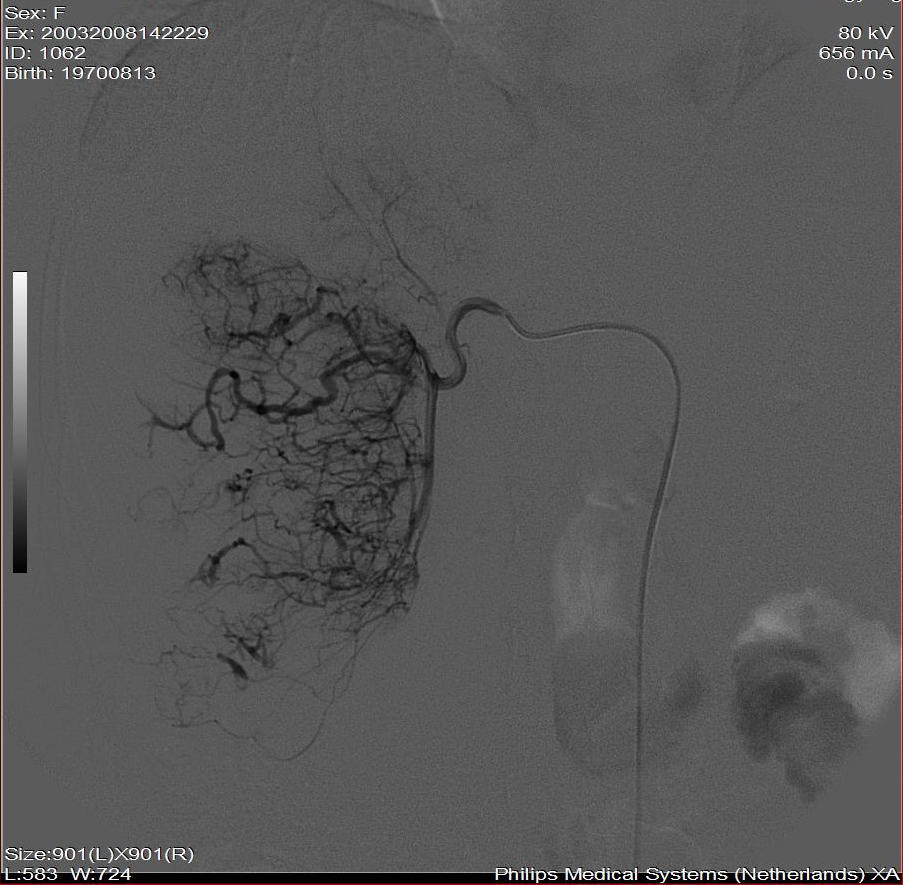

标题: DSA0138:F38Y,肝脏病变

第一次:

好牛的,右肝动脉发自肠系膜上动脉,不用微导管分次进行末梢栓塞,肿瘤染色完整。再次学习了。